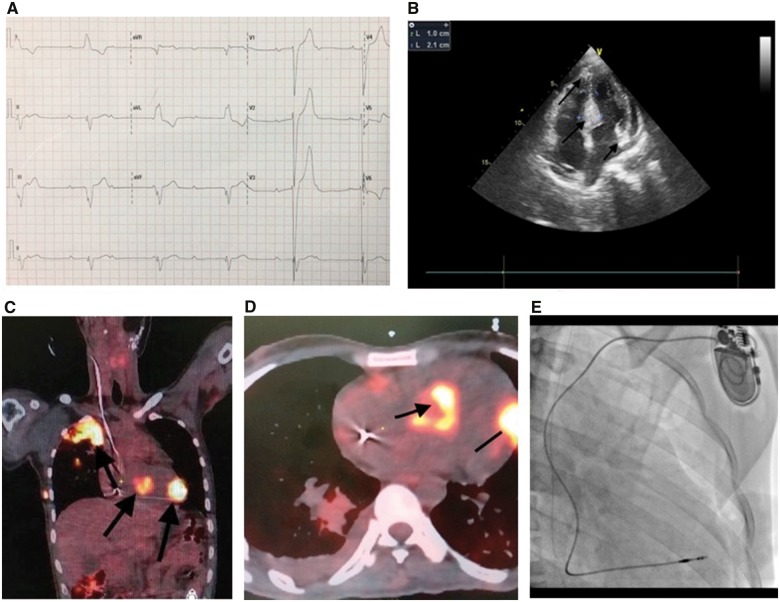

We report a 28-year-old man who was suffering from carcinoma of tongue and underwent hemimandibulectomy and post-operative radiotherapy. A histological diagnosis of squamous cell carcinoma was made. Three months later, he presented with multiple episodes of syncope to the emergency department. ECG showed CHB and a broad complex escape with left bundle branch block morphology (Figure 1A). These episodes were sudden in onset with no preceding symptoms. On physical examination, the patient had bradycardia with a regular heart rate of 32/min and normal blood pressure. On auscultation the chest was clear and there were no murmurs heard. Routine blood investigations were normal with normal serum creatinine 1.1 mg/dL (0.6–1.4 mg/dL) and normal serum sodium and potassium of 4.1 meq/dL (3.5–5.5 meq/dL). Echocardiography was performed which showed normal left ventricular ejection fraction and no valvular abnormalities. However, there were hyperechoic areas and hypertrophy of interventricular septum and the posterolateral wall of left ventricle as well (Figure 1B). The patient was paced using a temporary pacemaker as the patient was symptomatic with multiple episodes of syncope and had CHB on ECG with escape rate of 32 on ECG. The chest X-ray showed a large solitary nodule in the right upper zone. A positron emission tomography (PET) scan was performed and was suggestive of multiple metastasis in the interventricular septum, the right atrium, and the LV wall along with a large pulmonary metastasis (Figure 1C and D). The patient also developed paraneoplastic syndrome in the form of hypercalcaemia with serum calcium of 14 mg/dL (normal range: 8.5–10.2 mg/dL) which resolved on administering fluids and zoledronic acid intravenously. However, the CHB persisted despite normal calcium levels, so a decision to implant a permanent pacemaker was taken. The patient was then taken up for permanent pacemaker implantation and an active fixation lead was positioned into the low septal position in order to avoid metastatic site on the mid septal region. An active fixation lead was chosen as it is the institutional protocol to use active fixation lead (Figure 1E). A sensed R wave of 7 mV was achieved with a pacing threshold of 0.6 mV indicating a good position. Post-procedural ECG showed a ventricular paced rhythm. On the fifth day post-pacemaker implantation, the patient had massive haemoptysis. Crystalloids, and blood were transfused, but the patient succumbed before he could be taken up for bronchial artery embolization.

Figure 1.

(A) An ECG showing complete heart block and broad complex escape. (B) Four-chamber two-dimensional echocardiography showing infiltration in the interventricular septum and left ventricle (black arrows). (C and D) Secondaries in the positron emission tomography–computed tomographic images in coronal planes and transverse planes are shown. (E) Post-PPI image.